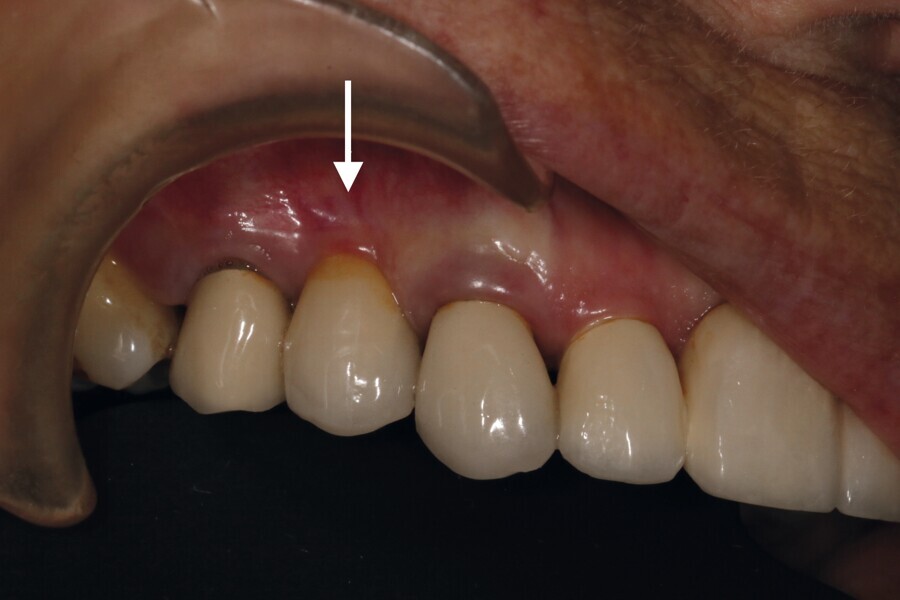

Une dent provisoire transvissée est confectionnée sur un pilier PMMA par couches successives de composite (Fig. 30). La couronne définitive céramo-zircone sur pilier variobase est transvissée à quatre mois. Un contrôle à deux ans montre une stabilité de l’environnement parodontal (Fig. 31).